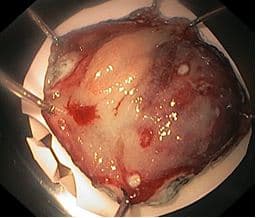

Извлечение удаленного препарата, гемостаз.

Эпителиальное новообразование извлечено для гистологического исследования при помощи петли захвата для инородных тел.

При его контрольном осмотре границы резекции в пределах здоровых тканей.

Резецированный участок слизистой оболочки растянут и закреплен булавками на пенопласте слизистой наверх, фиксирован в 10% растворе нейтрального формалина.

На рисунке: Резецированный участок слизистой оболочки, растянутый и закрепленный булавками на пенопласте слизистой наверх, фиксирован в 10% растворе нейтрального формалина.